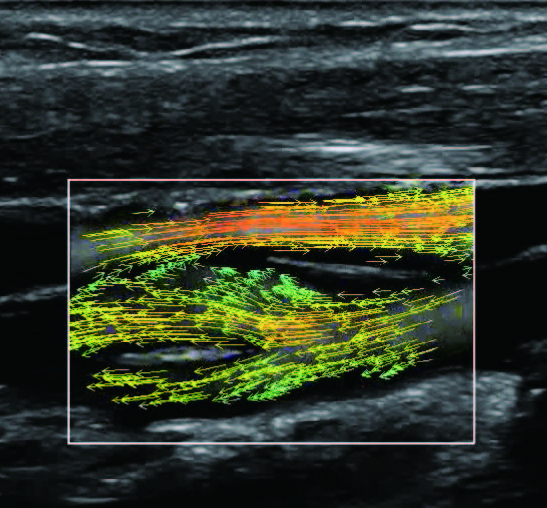

На изображениях, приведенных ниже показаны примеры из клинической практики врачей ультразвуковой диагностики, полученные в процессе апробирования прибора Mindray Resona 7. Приводится наглядные примеры сравнения традиционного режима ЦДК и режима V Flow (Vector Flow).

Изображена яремная вена и бифуркация сонной артерии. CAA, ICA и ECA показаны на одном изображении. В режиме ЦДК отсутствует подробная гемодинамика. В режиме V Flow отображаются данные о скорости и направлении движения частиц крови во всей зоны интереса, включая изменения характеристик кровотока в сонной артерии и яремной вене.